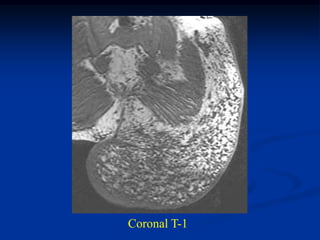

Case #1198                Axial T-2 MRI

62 year male with well-differentiated liposarcoma thigh

Coronal T-2 MRI